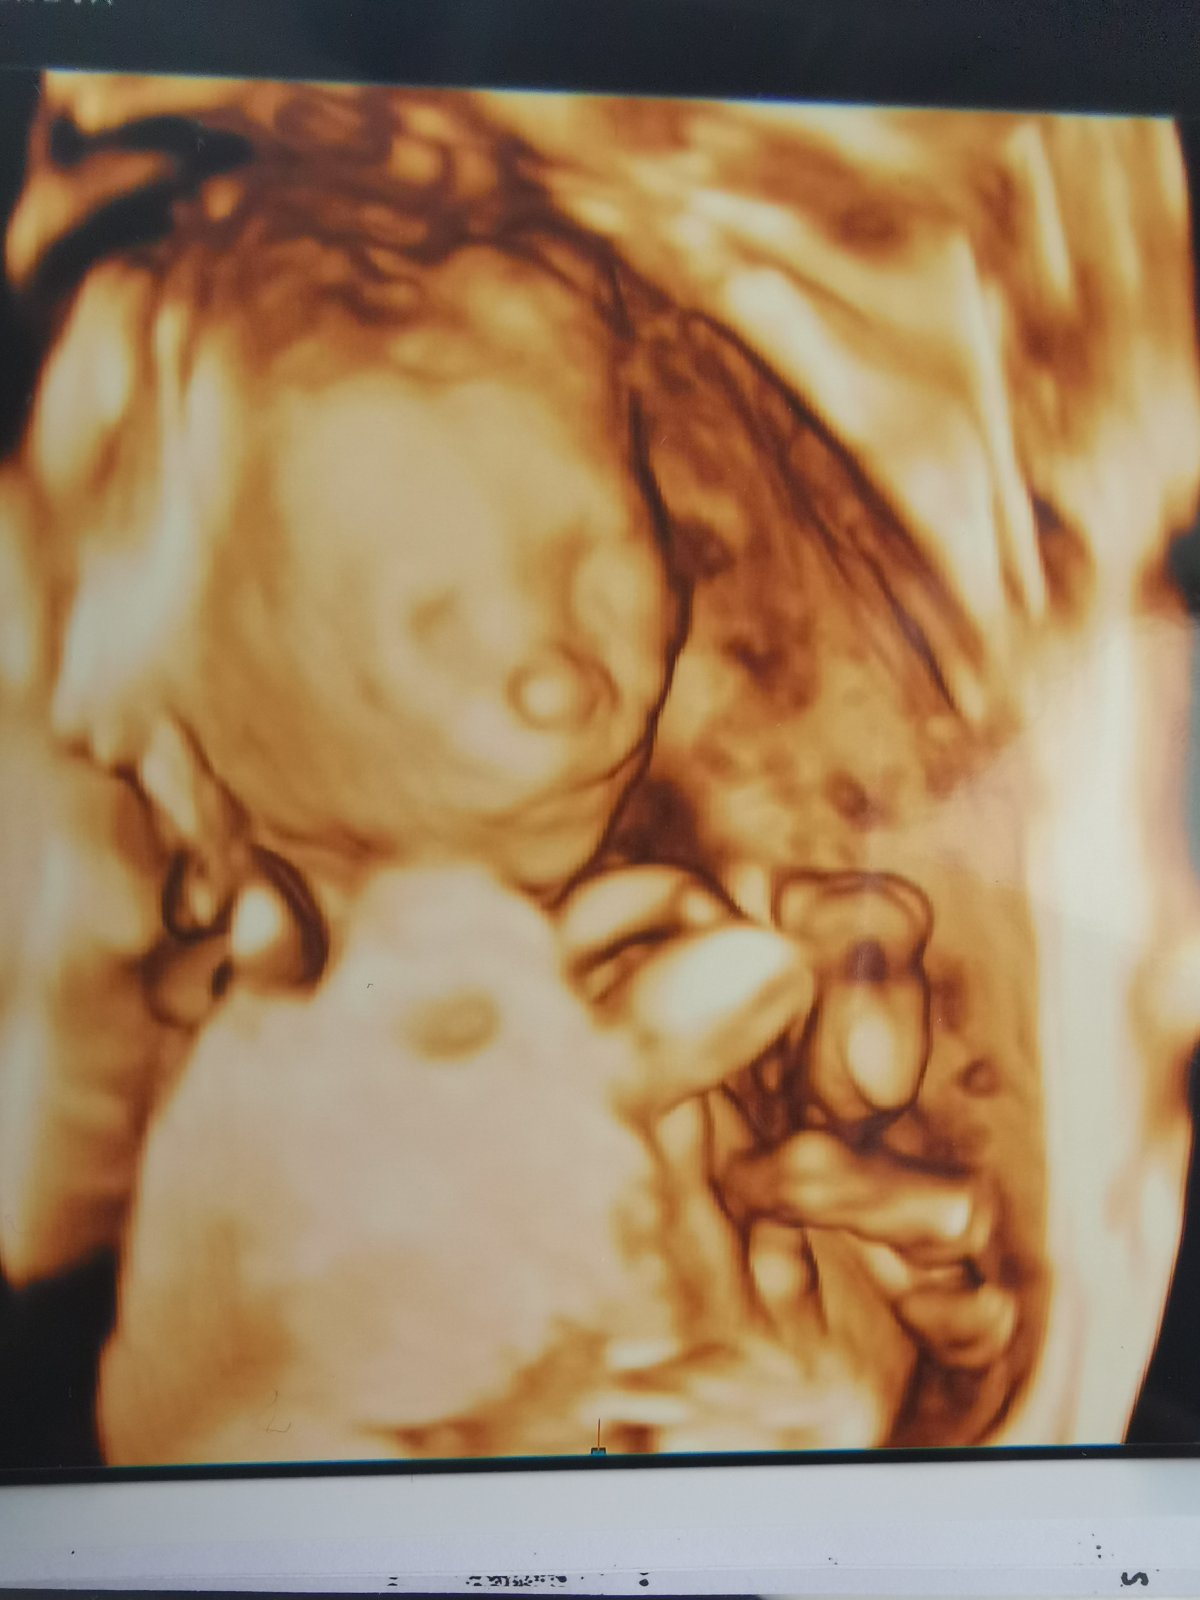

@juliemichal Ty už plánuješ páté kolo😂. Teď v předposledním dílu pořadu Malé lásky se měl taky narodit několikrát potvrzený chlapeček a narodila se holčička 😄. Já už toto těhotenství prožívám těžce a už nechci 😂. Doktor u mě na 3d nakonec řekl chlapeček taky, ale byl to boj 😲. Ještě jdu na velký ultrazvuk a pořád doufám že se pletou 😁

@pavlinkadv Aha, no i tak to jde špatně vidět, ale u Vás bych řekla spíše chlapeček, zdá se mi, že se tam něco stohuje nahoru 😉